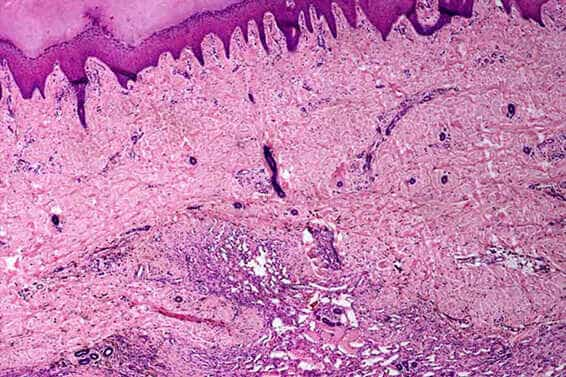

4. Дијабетички улкуси – компликације на удовима дијабетичара са отвореним ранама које узрокују да гној постане некротичан. Често захтева ампутацију или може довести до смрти.